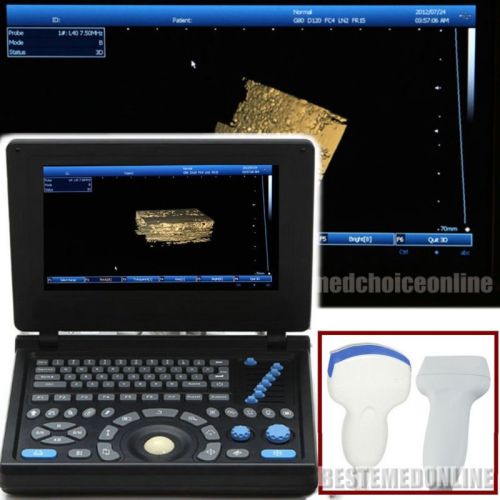

3D PC Platform Full Digital Laptop Ultrasound Scanner+ Convex &Linear BEST CHOIC

HOT HOT HOT! Digital Ultrasound Scanner 4-frequency Convex +Linear probes +3D

3D Digital Ultrasound Scanner +Convex TV 2 probes Optional 2 probes+3 years warr

ONLY 1-MONTH SALE!!! Digital Laptop Ultrasound Scanner Diagnostic + Linear 3D

NEW Full Digital TFT LCD Ultrasound Scanner High-resolution (built-in 3D) CONVEX

FULL DIGITAL Portable Ultrasound Scanner 3 probes "Convex,Linear,TV" +3D GOOD+++

3D Full-digital Ultrasound scanner machine with 3.5MHz R60 convex +2 USB Ports

Hot 3D Full-digital Ultrasound scanner machine W CONVEX +2 connectors+2USB ports

3D 10.1" Full Digital Laptop Ultrasound Scanner Machine +Micro-convex Probe CE

in 3D Full Digital Laptop Ultrasound Scanner (PC) with convex probe Free Ship

NEW 10.4" 3D PC platform Full Digital Laptop Ultrasound Scanner+ 3.5Convex Probe

+Aluminum box Full Digital 3D PC LAPTOP Ultrasound Scanner vaginal NEW